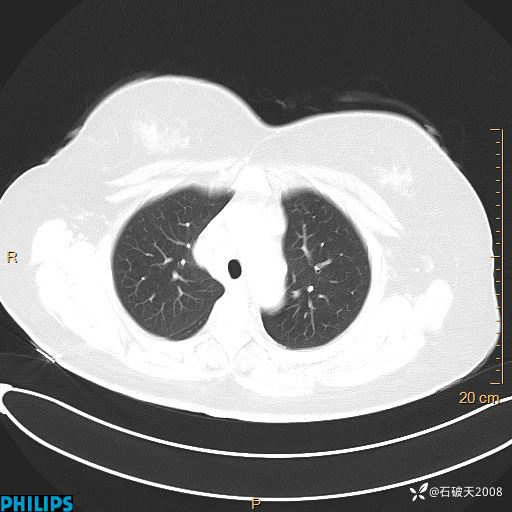

肺结节病?纵膈型肺癌?淋巴瘤?有点意思,欢迎围观

女 52岁 主 诉:咳嗽10余天,咳痰2天。

现病史:10余天前无明显诱因出现咳嗽,呈阵发性干咳,伴咽喉部发痒,无咽痛,无咳痰,无鼻塞、流涕、打喷嚏,无发热、畏寒、寒颤,无头痛、头晕,无胸闷、胸痛,无反酸、烧心,无腹痛、腹泻,无尿频、尿急,无皮疹等,在当地诊所求治,给予口服药物治疗(具体不详),病情无好转。遂在当地社区卫生服务中心开具口服药物治疗(具体不详),疗效欠佳。2天前出现咳痰,在我院门诊求治,行胸部CT提示肺部感染,建议住院,患者要求口服药物治疗,目前仍咳嗽、咳白色粘痰,白天量多,夜间自觉喉部喘鸣音,遂再次来院就诊,以“肺部感染”为诊断收入院。发病以来,神志清,精神可,饮食可,夜间睡眠差,大小便正常,近期体重无明显变化。

肺窗